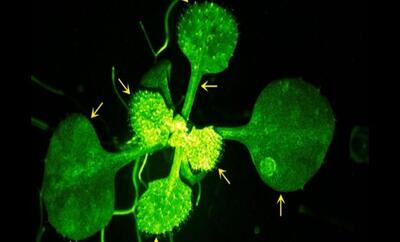

اندیشه معاصر - انقلاب در علم پزشکی/ احیای بینایی با استفاده از پیوند سلول های بنیادی برای نخستین بار در جهان اندیشه معاصر

دانشمندان ژاپنی توانستهاند با پیوند سلولهای بنیادی گرفته شده از سلولهای خونی انسان، بینایی را به افرادی که دچار آسیب قرنیه شدهاند، بازگردانند.